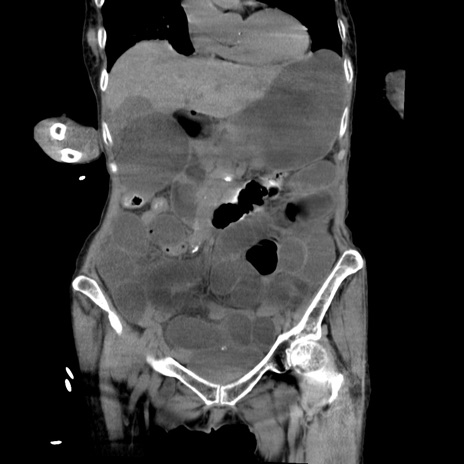

症例27(冠状断像)

【症例】80歳代女性

【主訴】嘔吐、腹痛

【現病歴】数時間前より嘔吐あり。心窩部痛出現し、徐々に右下腹痛あり。その後も数回嘔吐あり救急搬送となる。

【既往歴】左大腿骨頚部骨折手術

【身体所見】腹部は膨隆しているが軟らかく圧痛なし。腸雑音はやや亢進。

【データ】WBC 12000、CRP 19.05